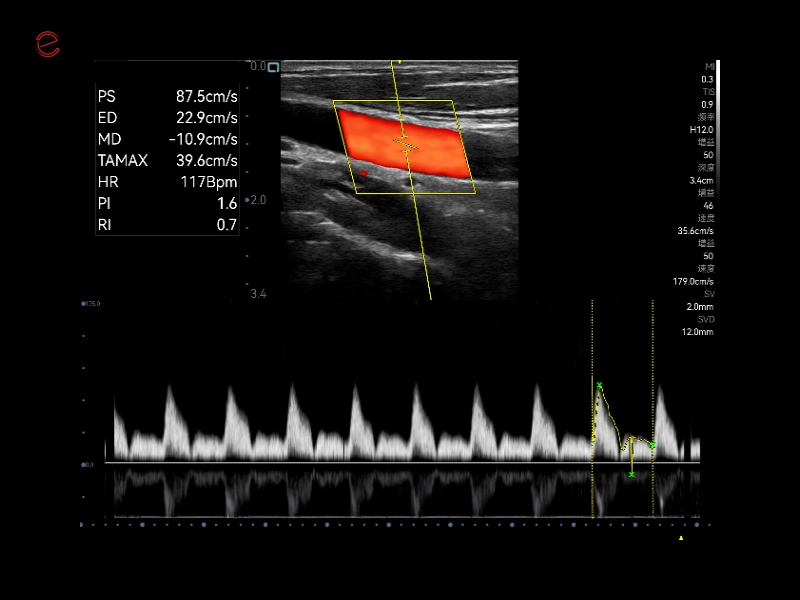

MyLab™C30 - Polm - Doppler

MyLab™C30 - Polm - Doppler

MyLab™C30 - Vertebral PW

MyLab™C30 - Vertebral PW